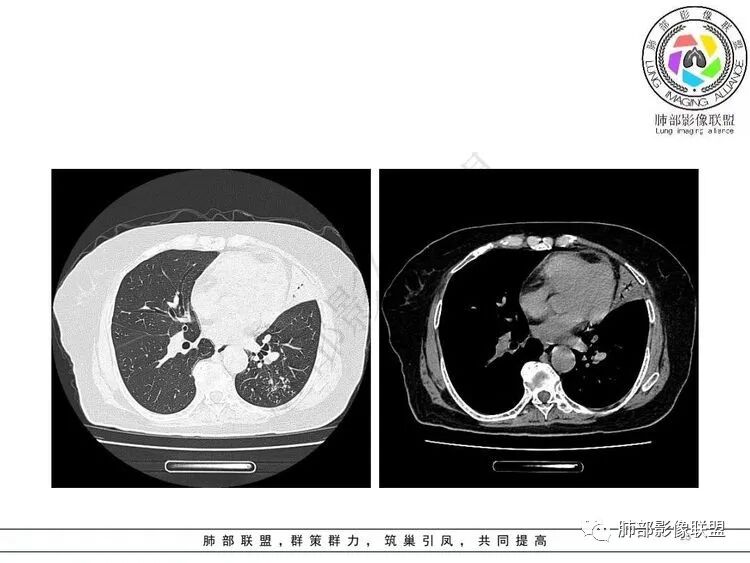

老年女性,呼吸衰竭,不发热,影像左肺上叶实变,支气管扩张,下叶小结节,t细胞检测阳性 ,常规考虑结核,但不发热。结合血气,超声,是不是有肺栓塞

患者近期胸闷气促,D2高,低氧血症,肺动脉干增宽,确实需要警惕肺栓塞,可以做个CTPA排除一下。一元结核不太好解释主诉

南边:这个是左上肺基本没啥功能所致吧肺动脉粗了尘缘:晨读:一、肺栓,CTPA去证实,这个一定有的,二,结核?这个不一定是,也不一定有结果,3、间质性肺水肿,这个应该有,但结果不一定能体现出来。综上:考虑肺栓塞伴间质性肺水肿,结核待排。

影像特点支持结核。气促、左上肺病灶似乎不能解释I型呼吸衰竭加上D—二聚体明显升高、肺动脉干增粗,临床需要想到二元可能:肺结核合并肺栓塞可能,需要完善CTPA明确有没有肺栓塞,因为急性肺栓塞是急危重症。

2.纵隔左移。肺动脉增宽。

2.“胸闷、气促”以及呼衰的临床表现,难以以当前肺部的病灶加以解释。

D-二聚体升高,肺动脉成像等明确患者肺栓塞的存在!